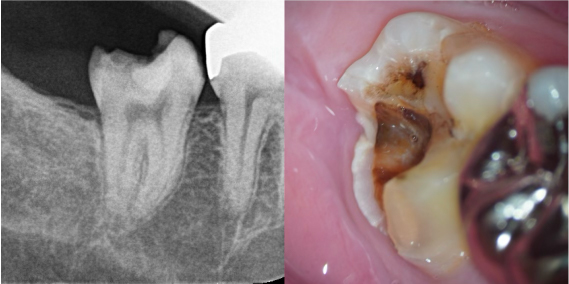

初診来院時の状態

元々入っていた銀歯が脱離し、内部で虫歯が確認できる状態でした。レントゲンでは、歯髄(歯の神経)に近接する深い虫歯が認められ、歯髄検査の結果から、すでに歯髄壊死(神経が死んでいる状態)であると診断できました。